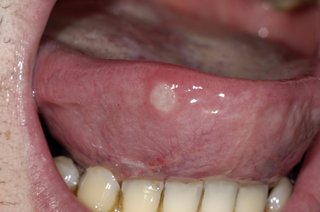

Wrzód ustny

Biało-szary okrągły ból po stronie języka wystający z ust

Okrągłe, bolesne i opuchnięte owrzodzenia, które wyglądają jak pęcherze